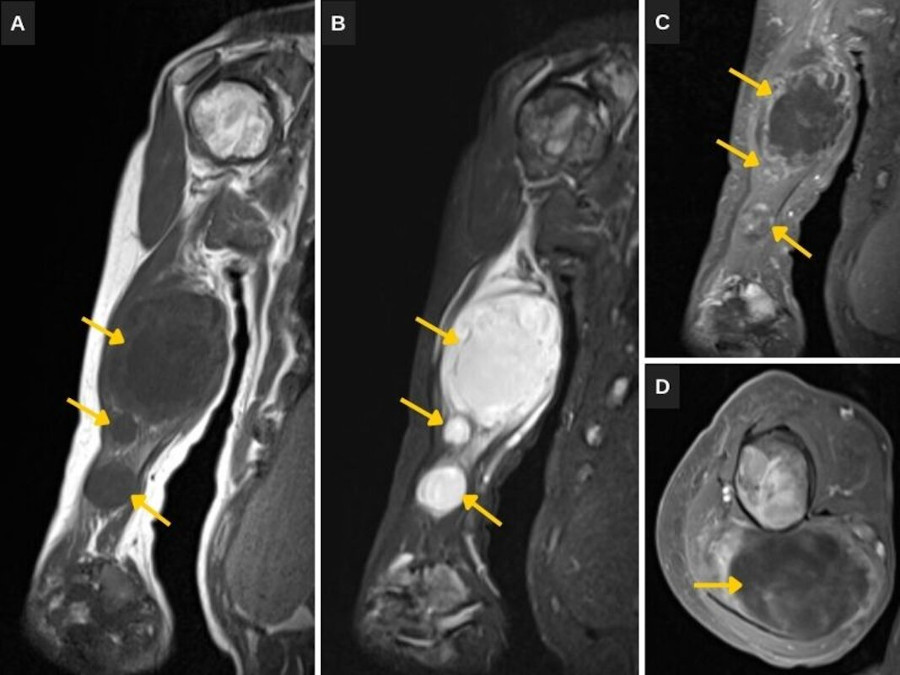

La RM muestra múltiples masas intramusculares en el brazo derecho (Fig. 1) y la región glútea izquierda (Fig. 2), de contornos netos, señal baja potenciada en T1 y alta en T2/STIR, y captación heterogénea del gadolinio.

Las masas intramusculares muestran las características típicas de mixomas por RM, que consisten en márgenes bien definidos, señal relativamente homogénea, baja en T1 y alta en T2/DP, y captación de contraste predominantemente periférica y central heterogénea. El realce periférico se debe a la presencia de abundantes vasos sanguíneos en la pseudocápsula, mientras que la captación central heterogénea se debe a septos fibrosos y tejido mixoide sólido10. Estas características, sumadas a la presentación clínica, su multiplicidad y la localización típica adyacente a la displasia fibrosa, permiten diferenciar los mixomas de otras lesiones quísticas de naturaleza más homogénea y de algunos sarcomas de partes blandas.